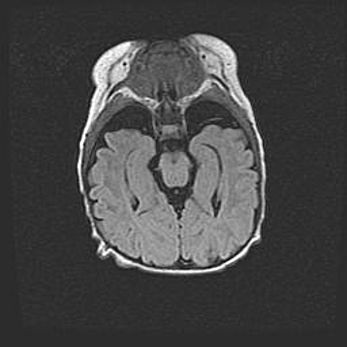

Церебральная ишемия II.

Возраст: 5 дней

Вес: 3400 г

Пол: женский

Окружность головы: 35 см

Срок гестации: 39 недель

Церебральная ишемия – это заболевание, характеризующееся недостаточностью (гипоксией) либо полным прекращением (аноксией) снабжения мозга кислородом по причине закупорки одного или нескольких сосудов. Это приводит к  что метаболическим расстройствам различной степени тяжести в тканях головного мозга, развитию коагуляционных некрозов и гибели нейронов.